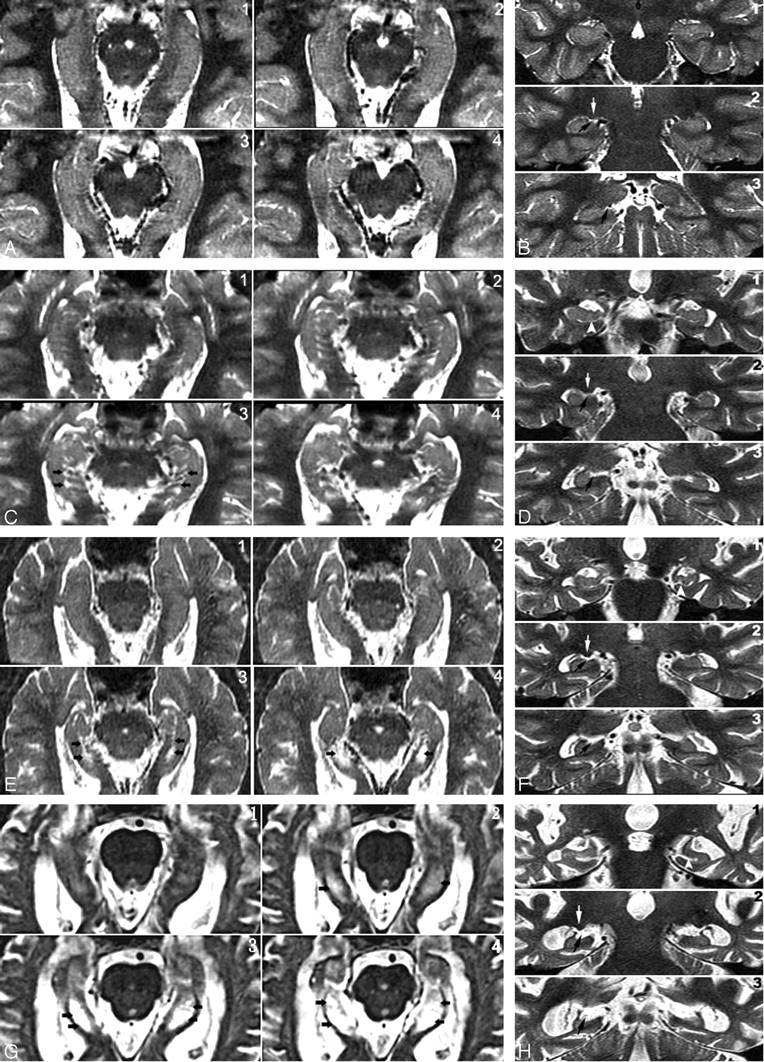

Four-point subjective rating scale of the perihippocampal fissures (PHF).

A and B, Axial and coronal view of same case. Left = 0; right = 0

C and D, Axial and coronal view of same case. Left = 1; right = 1

E and F, Axial and coronal view of same case. Left = 2; right = 2

G and H, Axial and coronal view of same case. Left = 3; right = 3

Axial images were reformatted in 1-mm thickness from inferior to superior, paralleling to the long axial of hippocampus. Black arrows highlight the PHF. There are 3 coronal views for each case showing the head, bodyi and tail of hippocampus. Black arrows highlight the PHF. White arrows on coronal plane show lateral geniculate body. Arrowheads on coronal plane show uncal sulcus.

The perihippocampal fissures (PHFs) include the lateral part of the transverse fissure, the choroidal fissure, and the hippocampal fissure.2(Fig 2A, -B) The transverse fissure is the lateral extension of the ambient cistern, which separates the thalamus superiorly from the perihippocampal gyrus inferiorly. The superior lateral extension of the transverse fissure is the choroidal fissure, which extends superior to the hippocampus. The inferior lateral extension of the transverse fissure is the hippocampal fissure, which extends between the cornu ammonis and the subiculum (Fig 2). The uncal sulcus may be noticed in the head of hippocampus (Fig 3G, H). We used a 4-point subjective scale to rate the size of the perihippocampal fissures on the axial T2 images.2 The PHF in all cases were rated independently by 2 radiologists (Y.L. and J.Z.) blinded to patient clinical status. The intraclass correlation coefficient for inter-reader reliability was 0.95. For all cases with disagreements in the ratings, a final consensus diagnosis was achieved. For each hemisphere, PHF was rated on the axial T2 imaging by using the following atrophy scoring: 0, none; 1, questionable; 2, mild/moderate; and 3, severe2 (Fig 3). An individual subject’s total PHF score was determined by summing the scores across hemispheres.